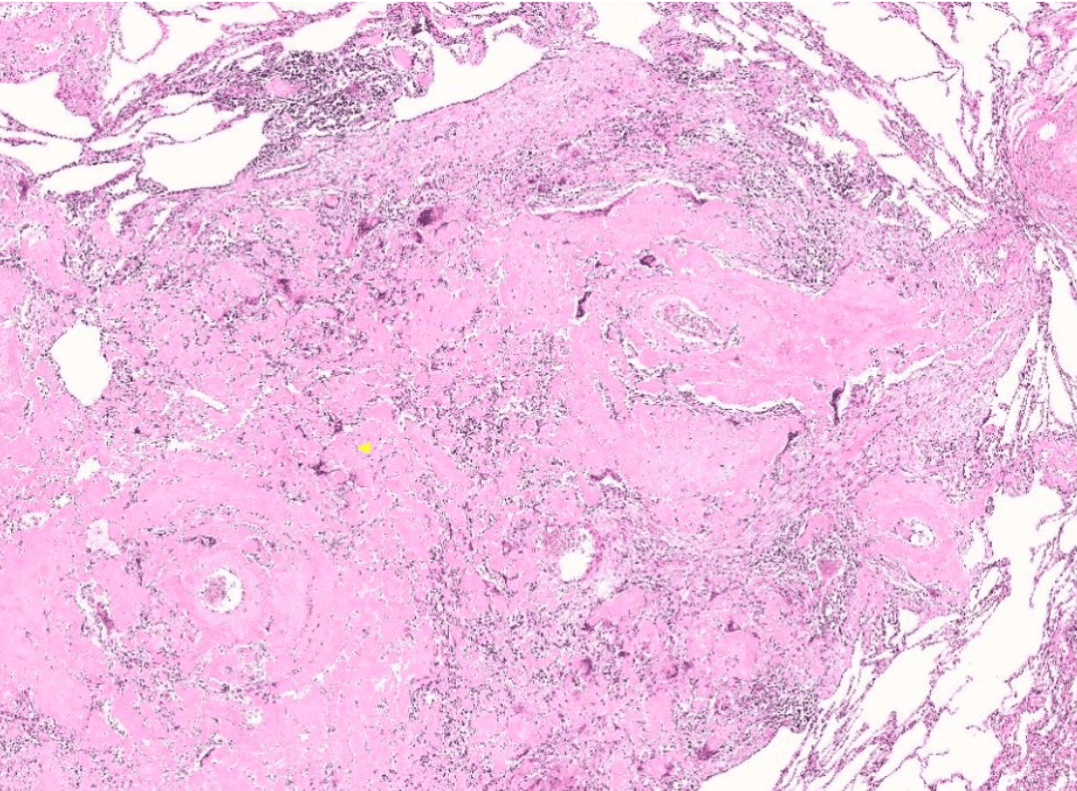

endometrial cancer